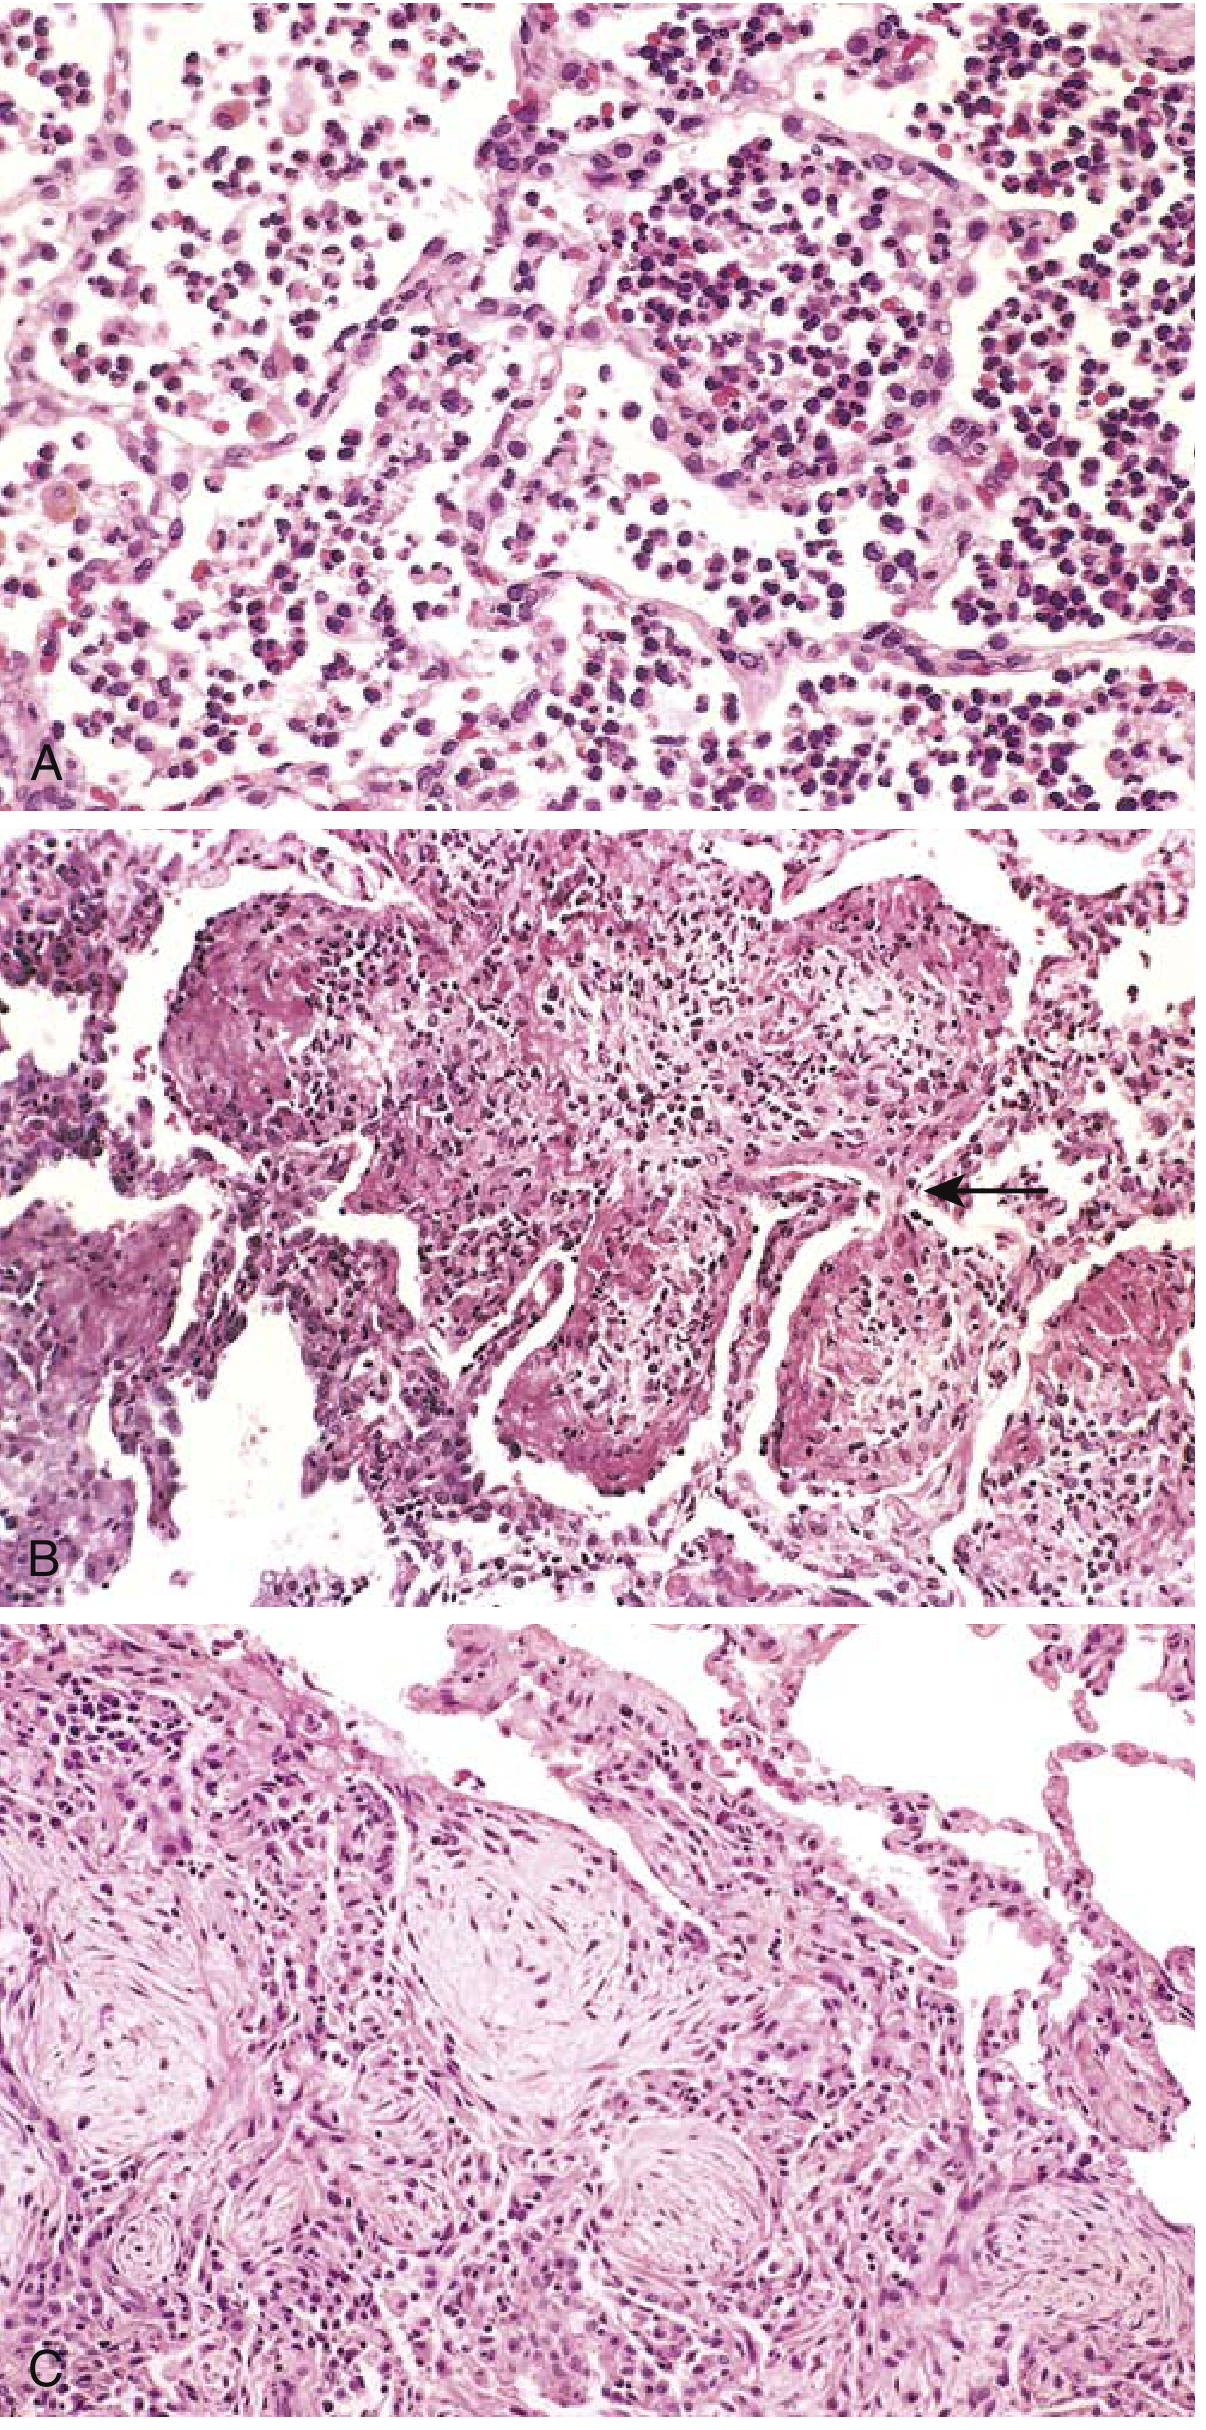

Histopathology of the stages of pneumonia

(A) Red hepatization — congested capillaries, massive neutrophilic exudate in alveoli. (B) Gray hepatization / early organization — exudate streaming through pores of Kohn (arrow). (C) Advanced organizing pneumonia — fibromyxoid masses with macrophages and fibroblasts. — Robbins & Kumar Basic Pathology